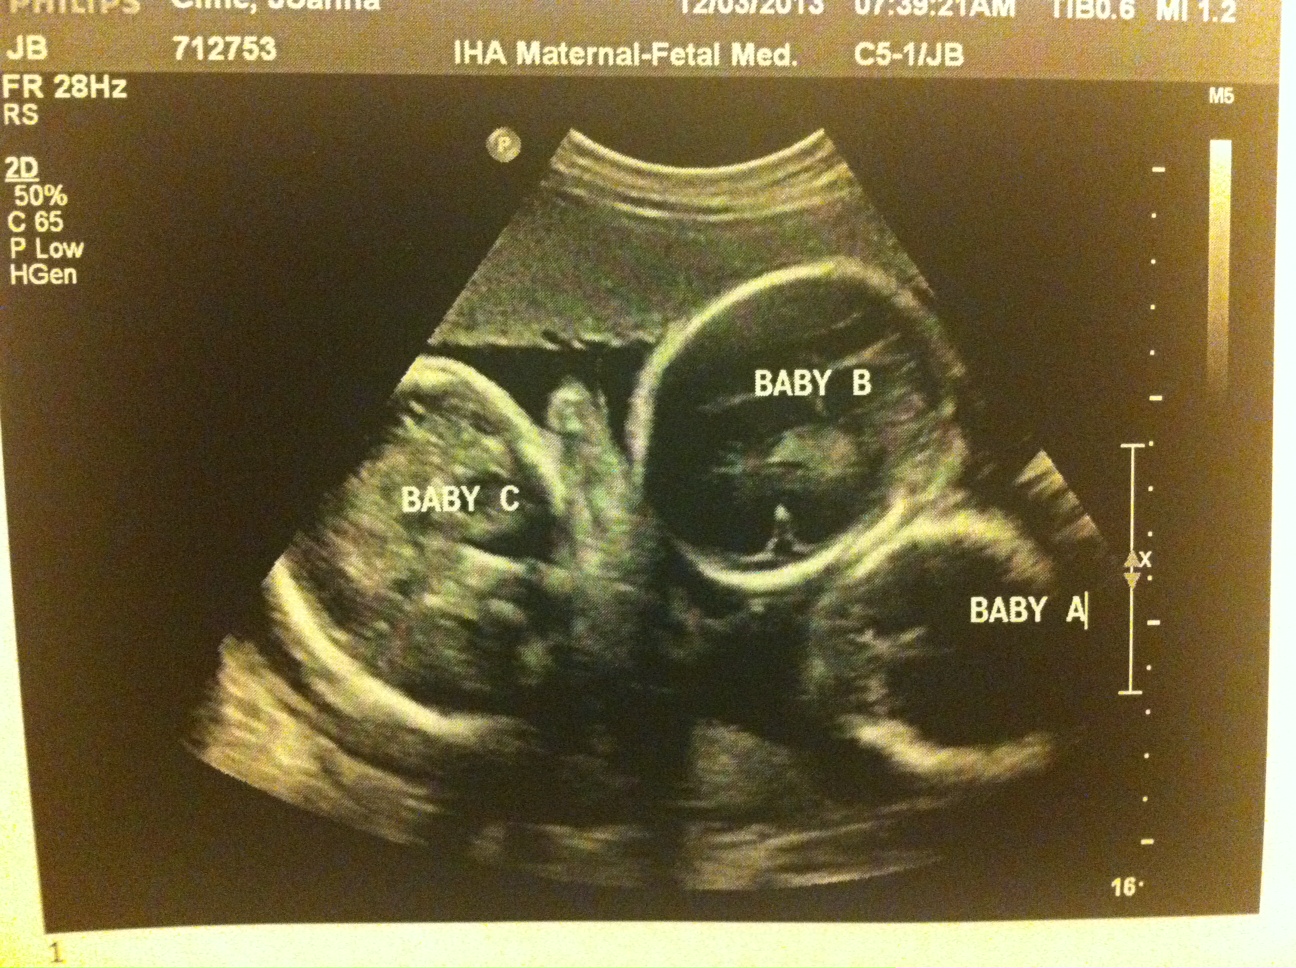

30w1d today and everything still looks great! All three babies have good fluid and there are no noticeable changes from last week. My doctors are optimistic that I’ll make it to my scheduled c-section at 25w2d (2/5/14). I’m a bit more cautious and still just taking it day by day but I’m encouraged.